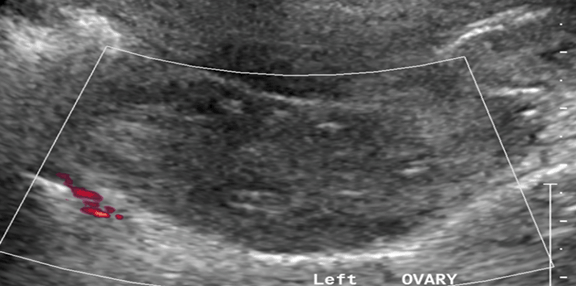

An abdominal-pelvic ultrasound revealed an enlarged left ovary, 20.9 cm3 volume with no evidence of blood flow on Doppler studies favoring a diagnosis of ovarian torsion (Figure 1). She underwent an emergency laparoscopy where the left adnexa were found to be twisted and dark (Figure 2). The right ovary was examined during the surgery and found to be normal. The left adnexa was detorted (Figure 3) but oophoropexy was not performed. However, on checking of the perfusion to the left ovary, it was found to be intact with fresh bleeding visible and change of color of the adnexal tissue to pink. A small incision on the ovary did not reveal any cyst or mass. The surgery was completed with no complications. Postoperative symptoms were pain on the port sites with mild nausea that was managed well with oral analgesics and antiemetics. The patient recovered well from the surgery and was allowed home on the second postoperative day. On follow-up after two weeks the patients had no symptoms and revered fully.

Figure 1: Ultrasound of the left ovary showing diminished Doppler flows.

Although laboratory tests may not be diagnostic of pediatric ovarian torsion, tests like a full hemogram, pregnancy test and kidney function tests may be useful as initial tests [6] . They will in most instances be normal but are useful in ruling out differential diagnoses such as pelvic inflammatory disease and ectopic pregnancy [7] . The laboratory tests conducted in the current patient were all normal and did not point to a certain differential. The best imaging test to diagnose pediatric ovarian torsion is usually a pelvic ultrasound with Doppler evaluation of ovarian blood flow [11]. The ultrasound examination may show a unilaterally enlarged ovary with a heterogeneous appearance due to edema and diminished or absent Doppler flows [12]. There may also be a whirlpool sign due to the twisting of ovarian pedicle and its vessels with peripherally displaced follicles due to ovarian edema [11]. The patient discussed had an enlarged ovary on ultrasound with diminished blood flow on Doppler which is in keeping with expected features. Adjuvant imaging such as computed tomography and magnetic imaging resonance at times may be needed to delineate ovarian anatomy further and rule out differentials although this methods are not commonly employed [6].